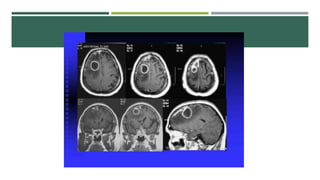

ABSCESO CEREBRAL

 Difícil diagnostico

 Cefalea, Fiebre, crisis convulsivas, focalización, síntomas de Hipertensión

Intracraneal

 Estadios:

 Invasión: Fiebre, somnolencia, disminución de concentración, cefalea. 1-2 semanas

 Localización: o Latente. Asintomática. Dura semanas.

 Crecimiento: Signos focales

 Terminación: Ruptura del absceso.

 TC, EEG, RM

ABSCESO CEREBRAL  Difícildiagnostico  Cefalea, Fiebre, crisis convulsivas, focalización, síntomas de Hipertensión Intracraneal  Estadios:  Invasión: Fiebre, somnolencia, disminución de concentración, cefalea. 1-2 semanas  Localización: o Latente. Asintomática. Dura semanas.  Crecimiento: Signos focales  Terminación: Ruptura del absceso.  TC, EEG, RM